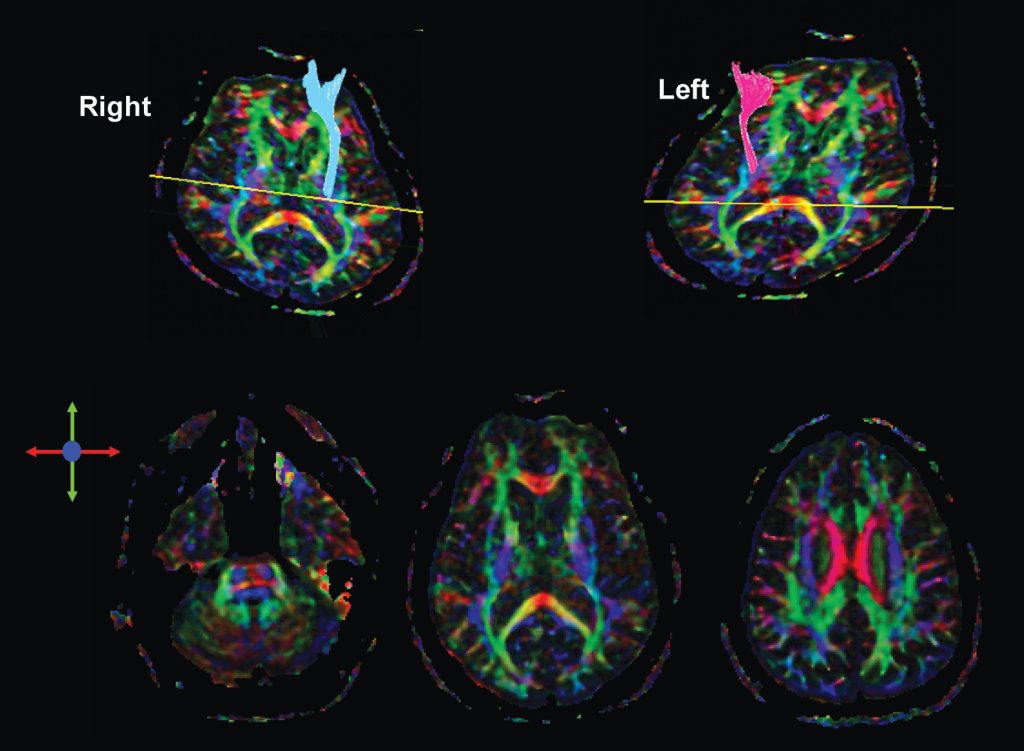

Tractography is a new magnetic resonance technique that enables mapping and, consequently, evaluation of different white matter tracts in the central nervous system. It encompasses acquiring a sequence called diffusion tensor imaging in a common 1.5 or 3 Tesla magnetic resonance equipment, independently or associated to conventional images of the study(–).

The acquired images are post-processed using several types of software – some are available online for free. The same acquisition of images allows calculating quantitative parameters, such as fractioned anisotropy (FA) and apparent diffusion coefficient (ADC), which interfere in white matter integrity, in addition to providing several maps, such as color map, identifying the orientation of diverse white matter tracts.